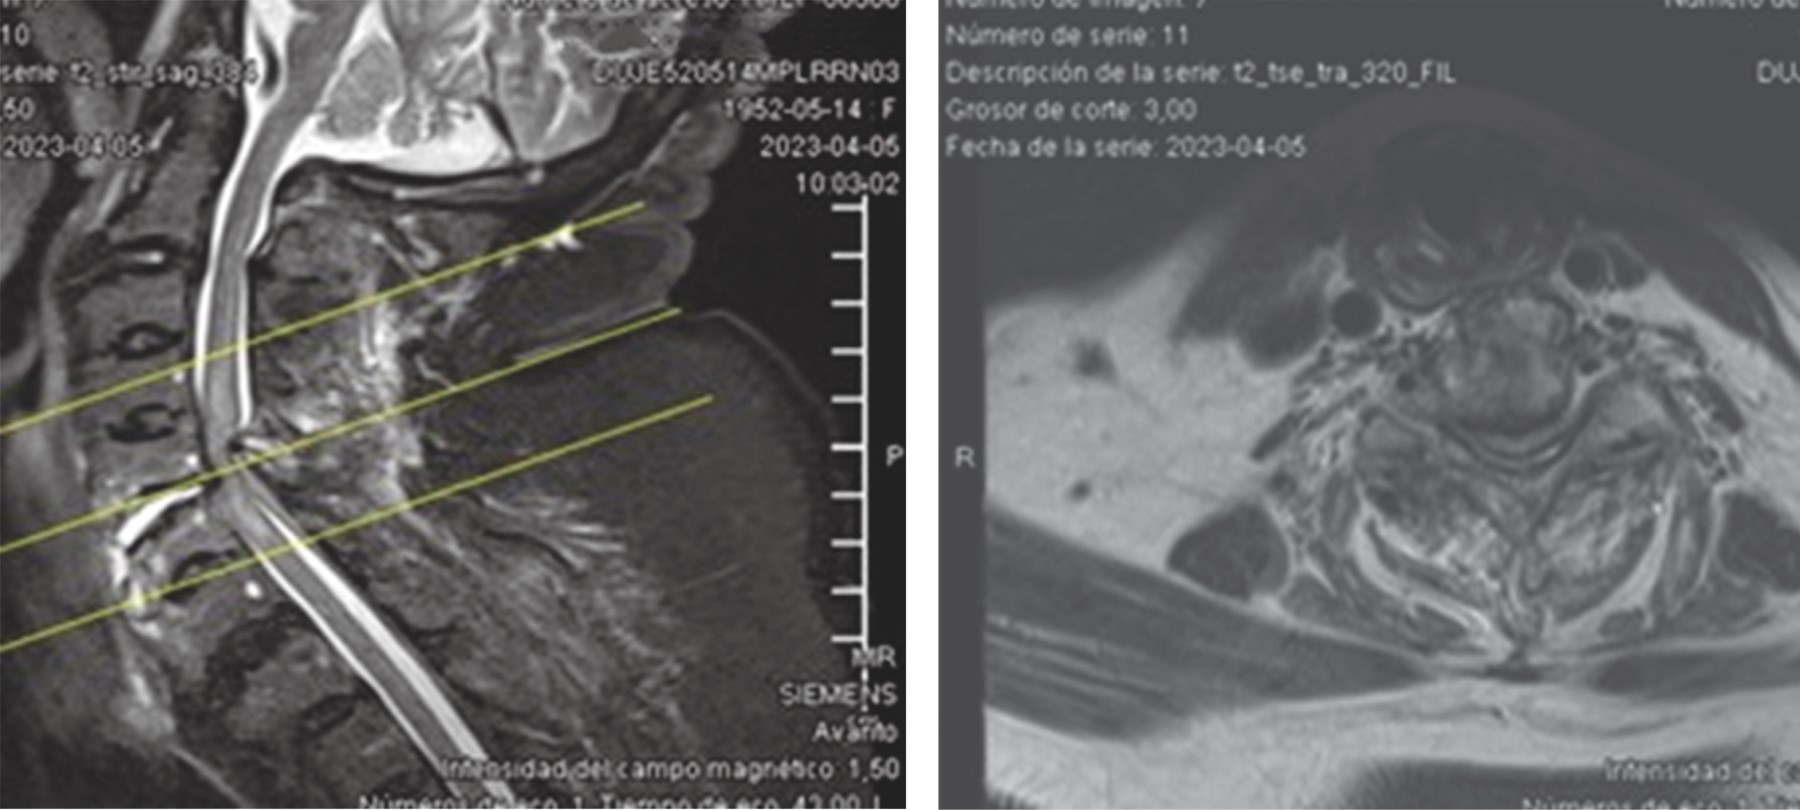

Diffuse idiopathic idiopathic skeletal hyperostosis (DISH), or Forestier's disease is a rare disease of unknown etiology. It is a systemic condition in which ossification of the anterolateral sides of at least four contiguous bodies, calcification of ligaments and entheses develops and is accompanied by spinal pain predominantly in the thoracic spine. In this case report we present a 70-year-old female patient presenting with DISH with complete spinal cord injury from c7 to distal on ASIA A scale following a fall from her own plane of support managed surgically with posterior cervical approach and instrumentation of lateral masses and decompression with good clinical evolution and partial clinical recovery to ASIA C.

Figure 3